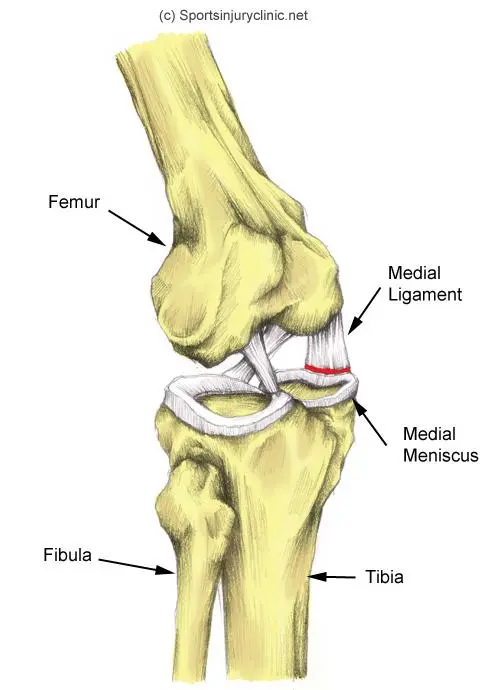

관절은 우리 몸의 운동 범위를 안전하고 넓게 가동할 수 있는 역할을 하게 됩니다. 이러한 관절 중에 팔의 중심부인 팔꿈치와 다리의 중심부인 무릎의 경우에는 여러 인대와 근육, 기타 구조물 들이 위치하고 있습니다. 무릎이 Lateral 에서 Medial 로 큰 충격을 받게 되면(Valgus force) 내측에 있는 구조물 들이 영향을 받게 되는데 아래 그림과 같은 매커니즘으로 손상을 입게 됩니다.

붓기가 빠진 후에 수술을 하는 경우가 많으며, MCL 과 medial meniscus의 손상여부를 파악 후에 ACL recon 등의 수술을 시행하면서 함께 시행해 볼 수 있겠습니다. (운동 선수들의 경우 기능적 회복을 위하여 수술을 필요로 하는 경우가 많습니다.)